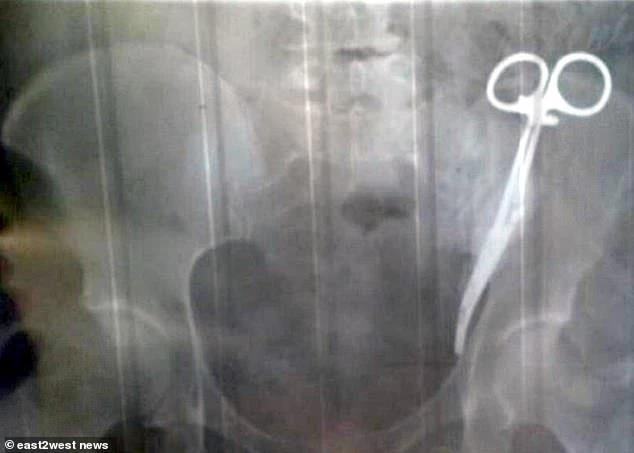

Vào năm 1996, bà Gobeeva mang thai và sinh mổ. Lúc bấy giờ bác sĩ đã bỏ quên một dụng cụ y khoa dài khoảng 15 cm trong bụng bà mà không hay biết. Ảnh: EAST2WEST NEWS

Vào năm 1996, bà Gobeeva mang thai và sinh mổ. Lúc bấy giờ bác sĩ đã bỏ quên một dụng cụ y khoa dài khoảng 15 cm trong bụng bà mà không hay biết.

Ban đầu, bác sĩ chụp X-quang nói rằng bà đang giấu một chiếc kéo trong túi áo, nhưng sau đó họ hoảng hốt phát hiện ra nó thực sự nằm trong bụng bà.

"Có một cái kẹp nằm bên trong bụng của bà", bác sĩ nói và cho bà Gobeeva xem hình ảnh X-quang.